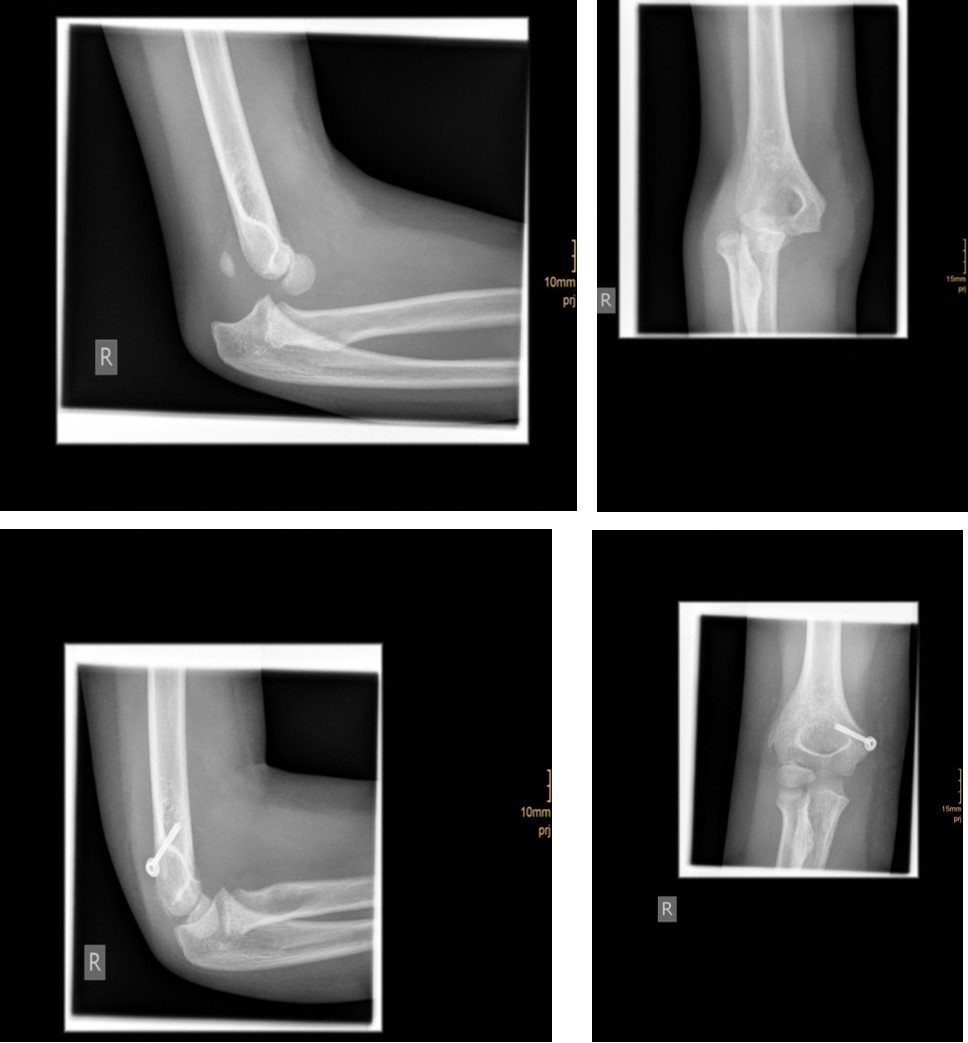

The fracture fragment can be approached by a posteromedial incision that allows good exposure of both the fracture site and the ulnar nerve. Fixation is easily achieved with smooth K-wires or with screws in older adolescents. Two wires are necessary because of the sagittal rotation forces exerted on the fracture fragment by the common flexor muscles. Figure 4 and Figure 5.

Figure 4.14 year old female patient with a elbow dislocation and a dislocated left epicondyle fracture which was treated by open reduction and osteosynthesis with two divergent Kirschner wires (personal collection)

Figure 5.9 year old female patient with a elbow dislocation and a dislocated right medial condyle fracture which was treated by open reduction and osteosynthesis with a screw (personal collection)